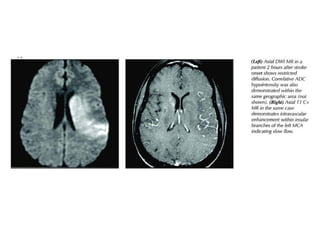

Diffusion Weighted Imaging (DWI)

DWI is the most sensitive sequence for stroke imaging.

DWI is sensitive to restriction of Brownian motion of

extracellular water due to imbalance caused by cytotoxic

edema.

Normally water protons have the ability to diffuse

extracellularly and loose signal.

High intensity on DWI indicates restriction of the ability of

water protons to diffuse extracellularly.

• Acute stroke causes excess intracellular water

accumulation or “cytotoxic edema”, with an overall

decreased rate of water molecular diffusion within

the affected tissue.

• Tissues with a higher rate of diffusion undergo a greater loss of

signal in a given period of time than do tissues with a lower

diffusion rate.

• Therefore, areas of cytotoxic edema, in which the motion of

water molecules is restricted, appear brighter on diffusion-

weighted images because of lesser signal losses.

• Hyperintense restriction from cytotoxic edema

• DWI improves hyperacute stroke detection to 95%

• High signal can persist up to 57 days post-ictus, (after 10

days, T2 effect may predominate over low ADC = "T2

shine-through")

• Corresponding low signal on ADC maps- May normalize

after tissue reperfusion, Note: Hyperintensity on ADC map

(T2 "shine-through") may mimic diffusion restriction